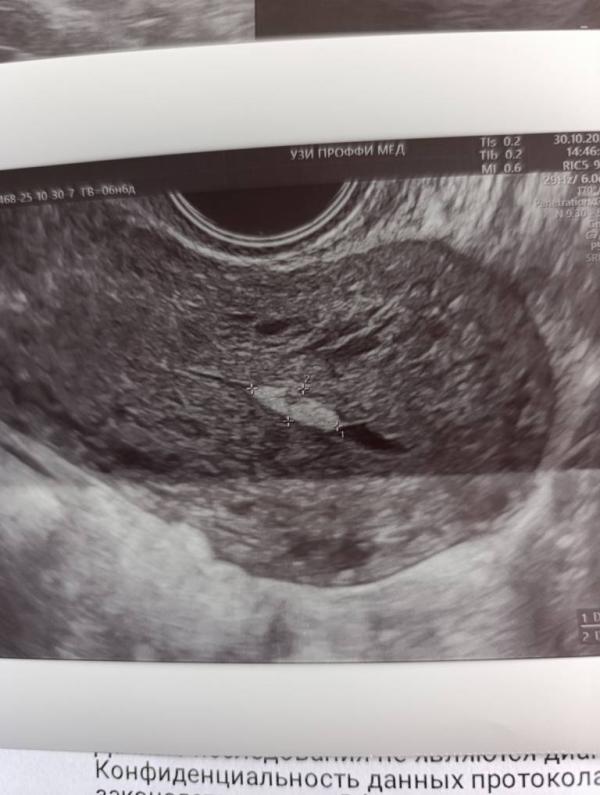

Сегодня была на УЗИ после родов, сказали есть что-то похожее на плацентарный полип. Ребенку два месяца, у меня до сих пор кровит. Мы на ГВ.